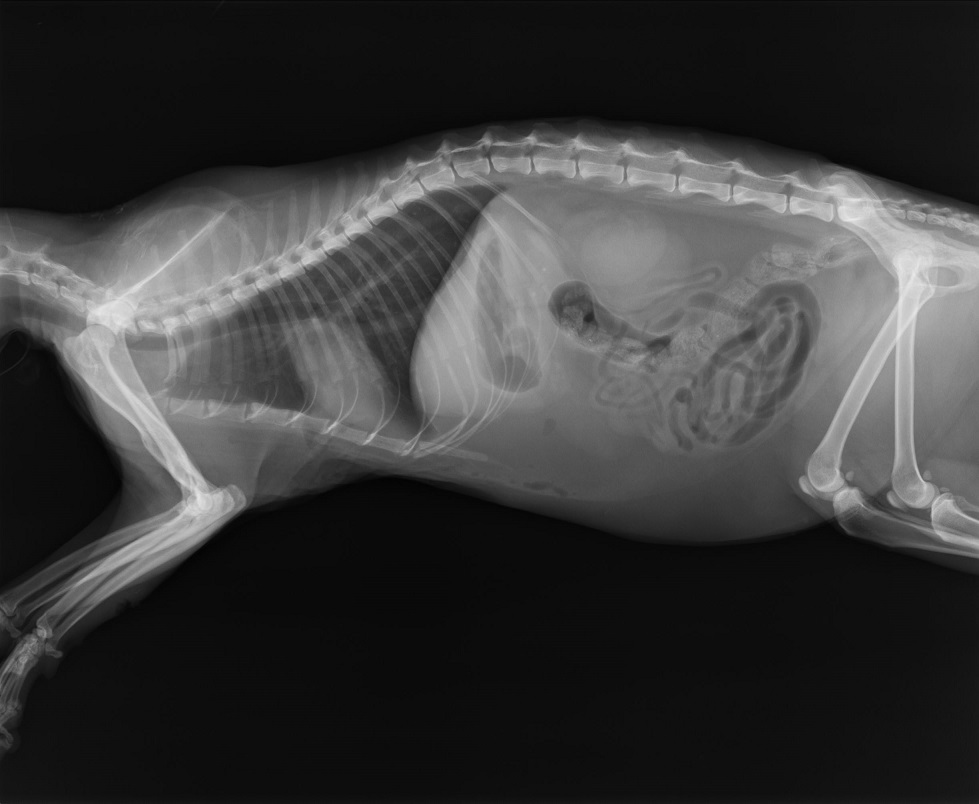

主題: 您好!請幫忙醫助被狗咬傷極嚴重的妙鼻貼!謝謝! 申請者姓名: 楊宜蓁 花色: 申請日期: 2015-06-03 23:42:31 申請者部落格: 申請者臉書網址: 所在縣市/合作醫院: 高雄市/恩澤動物醫院 治療費用: 6120元 需求人數: 7人 已結案 (2022-04-14 17:49:23) 報名人員: Joe Chen(已付款)、Chen Ping(已付款)、Zheng(已付款)、a-song(已付款)、Amber Chung(已付款)、安源企業社(已付款)、凱倫(已付款)、 候補人員: 動物病情說明: 我在昨天(5/30)晚上六點多出門時看到一隻貓蜷縮在花盆旁,

才發現他全身是傷非常虛弱,

我馬上回家籠子抓他要帶去醫院他也沒力氣反抗,

帶去醫院醫生說是被狗咬的撕裂傷,

這個情形應該已經超過七天了,

驗血之後說有敗血症,需要打抗生素,

腋窩的傷極為嚴重,可能會截肢,

失溫、脫水,血壓極低。